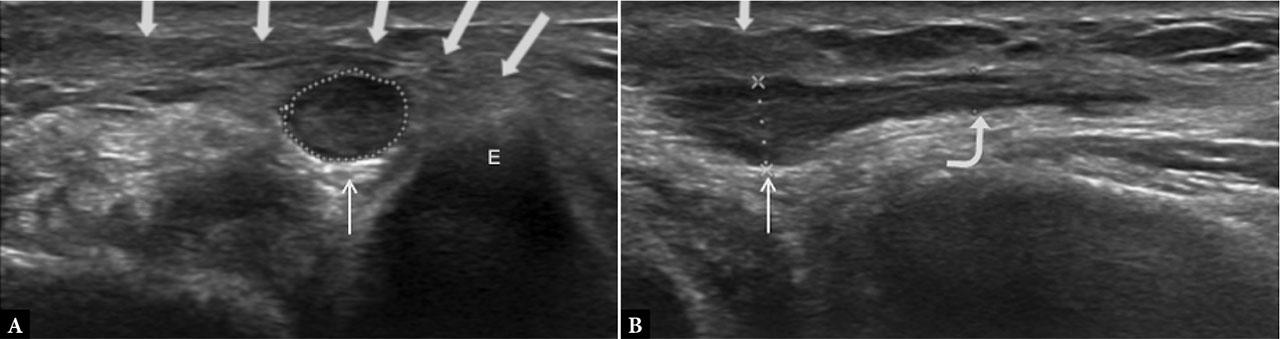

Common etiologies. Thickened Osborne’s ligament (humeroulnar aponeurotic arcade), often visualized as a compressive band over the ulnar nerve (Fig. 2). Anconeus epitrochlearis muscle is the most common structural cause of CuTS (present in ~10%–34% of individuals), which may replace Osborne’s ligament due to its analogous course and can compress the nerve with flexion(19). Fibrous or muscular hypertrophy resulting from repetitive strain (e.g., heavy manual labor, sports activities) may further contribute to nerve compression. Periarticular or articular conditions such as synovitis, osteoarthritic periarticular spurs, ganglion cysts, (osteo)chondromatosis, or joint effusion of the adjacent elbow, all of which may also lead to compression.

Ulnar nerve neuropathy due to compression by Osborne’s ligament. A. Transverse ultrasound view and B. Longitudinal ultrasound view at epicondyle level (E). The ulnar nerve appears hypoechoic, enlarged, and swollen (thin arrow). Osborne’s ligament is thickened (multiple thick arrows). Distally to the impingement, the ulnar nerve fascicular pattern is preserved (curved arrow)

Ultrasound findings. The nerve demonstrates a focal caliber change with maximal compression beneath Osborne’s ligament at ~135° of elbow flexion(20). The ligament may be thickened or replaced by an accessory anconeus epitrochlearis muscle with a triangular or trapezoid shape.